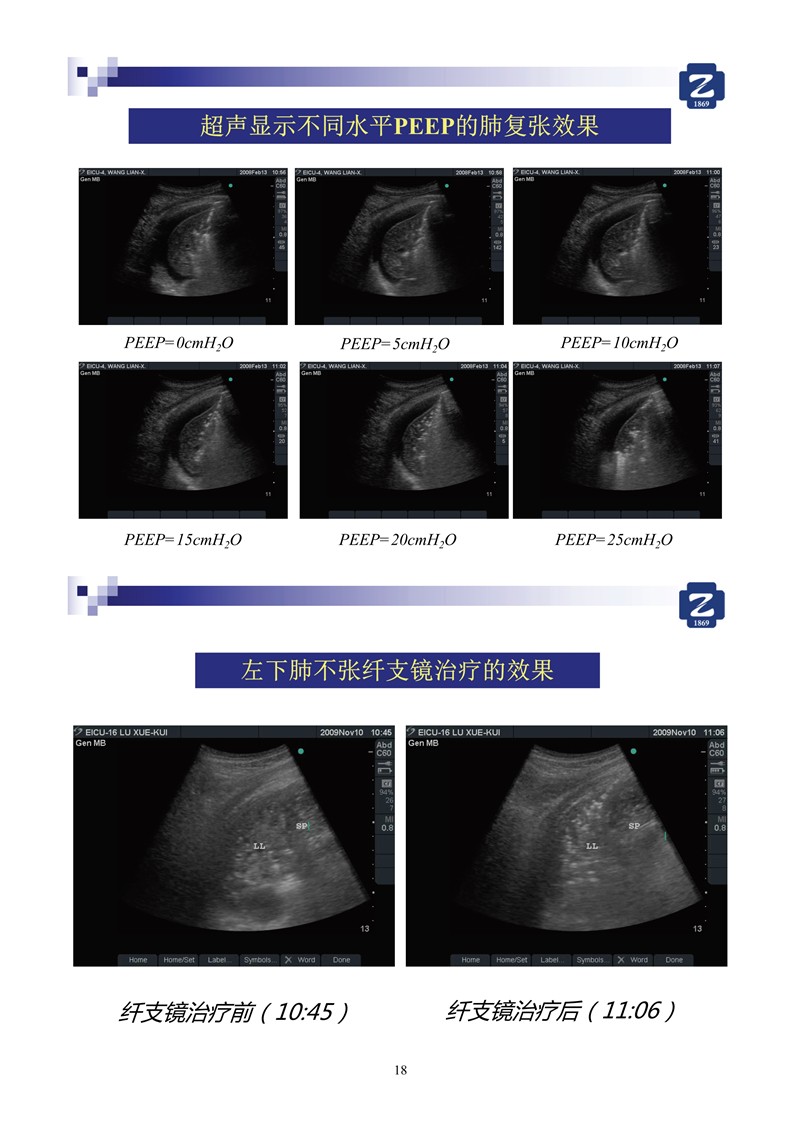

第一版新型冠狀病毒肺炎超聲診斷實(shí)用手冊(cè)(全文)

新冠肺超聲實(shí)用手冊(cè)(2)_35.jpg